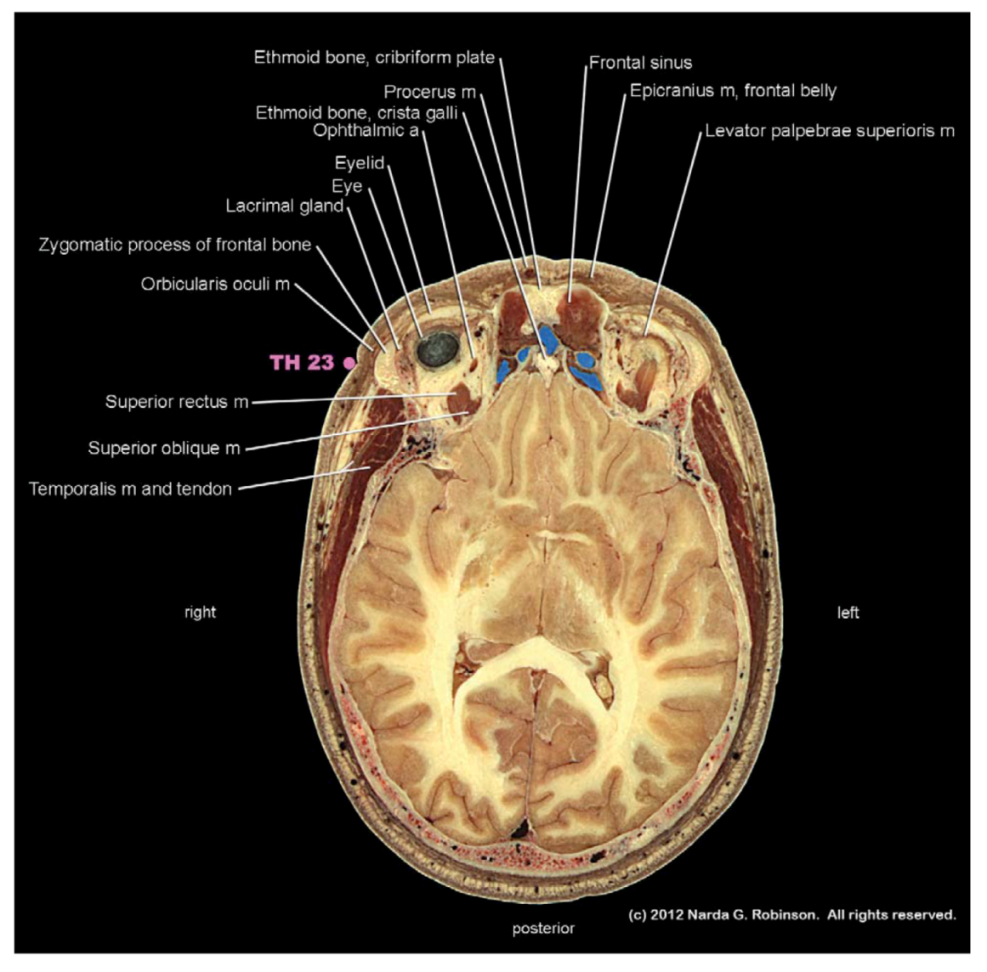

8.1. Head

- Robinson, N.G. Interactive Medical Acupuncture Anatomy; Teton NewMedia: Jackson, WY, USA, to be published in 2013.